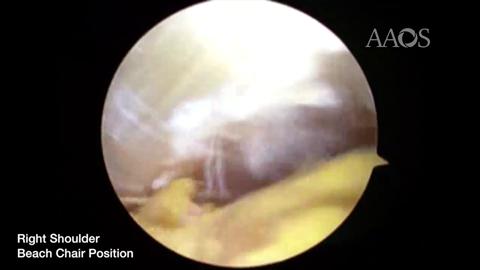

Arthroscopic Suprascapular Nerve Release

BACKGROUND: Suprascapular neuropathy is a relatively rare pathology associated with compression of the nerve, dynamic shoulder injury, and repetitive overhead motion. The suprascapular nerve has both sensory and motor components, thus neuropathy can present with posterolateral shoulder pain, weakness, and instability. A precise diagnosis is challenging and there remains controversy over how and when the nerve should be released in symptomatic patients. While treatment depends on the underlying etiology, for many cases there are no formal guidelines on how to best manage these patients. The purpose of this video is to illustrate the technique for arthroscopic suprascapular nerve release for symptomatic patients.METHODS: A review of the current concepts in suprascapular neuropathy is conducted. This video demonstrates suprascapular nerve release in a patient with suprascapular nerve entrapment at the transverse scapular notch. There is specific focus on relevant patient history, injury presentation, etiology, surgical indications, prognostic factors, surgical technique, concurrent procedures, and rehabilitation. The key steps of the procedure are highlighted, along with the rationale behind the approach.RESULTS: This video illustrates the important concepts in suprascapular nerve injury and an arthroscopic technique for nerve release. Sensory and motor function can be regained after this procedure and a course of postoperative rehabilitation.CONCLUSION: While suprascapular neuropathy is a relatively rare pathology, the diagnosis is often missed when it is present. The underlying etiology guides treatment of the patient, and therefore must be identified. Overuse injuries lacking signs of denervation respond reasonably well to conservative therapy. When surgical treatment is indicated, it should be adapted to the underlying etiology. Promising clinical outcomes have been seen for both open and arthroscopic approaches. However, specialized orthopaedic surgeons have been increasingly performing arthroscopic suprascapular nerve release since its inception. This video provides an up to date, standardized, and evidence-based guide for how to optimally manage patients with suprascapular neuropathy.